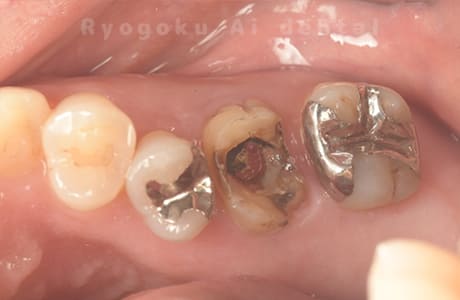

Case07

- 慢性根尖性歯周炎(16・17・15部)

- 治療内容

- マイクロエンド(3歯分)

- 308,000円(3歯分)※被せ物を除く

右上の違和感が取れないとのことで来院された患者さんです。ファイルという器具が歯の根の中で折れていることを説明し、マイクロスコープを使用した根管治療を提案し、治療を行いました。折れたファイルも取り除くことができ、現在の経過は良好です。